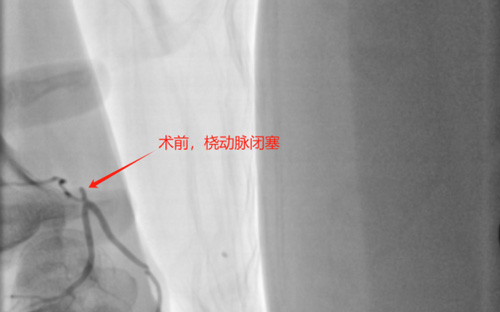

据了解,患者龙某,55岁,因冠心病,先后经桡动脉造影及介入治疗3次,最后一次从左手近端桡动脉介入治疗,平素规范口服相关药物,本次入院拟复查造影。术前评估远端桡动脉搏动稍弱,近端桡动脉搏动弱,考虑桡动脉闭塞,常规穿刺远端桡动脉并成功,桡动脉造影提示发现近端桡动脉闭塞,心血管内科介入团队经过讨论后决定先尝试经同侧远桡动脉逆向开通闭塞近端桡动脉,使用sion、PILOT50、XTA导丝分别尝试最终通过桡动脉闭塞段,使用球囊全程扩张桡动脉,然后造影可见桡动脉顺利开通并完全显影,同时并顺利完成冠状动脉造影。